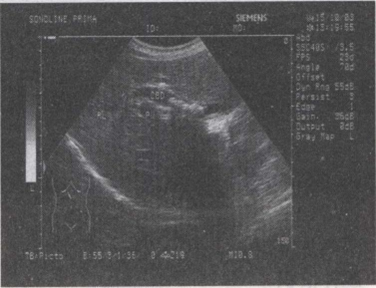

50.女,48岁,上腹部剧烈疼痛2天。皮肤巩膜轻度黄染。声像图如图所示,诊断为()

49.女,53岁,上腹部疼痛不适半年余,皮肤、巩膜黄染进行性加重。B超检查如图所示,根据超声声像图诊断为()